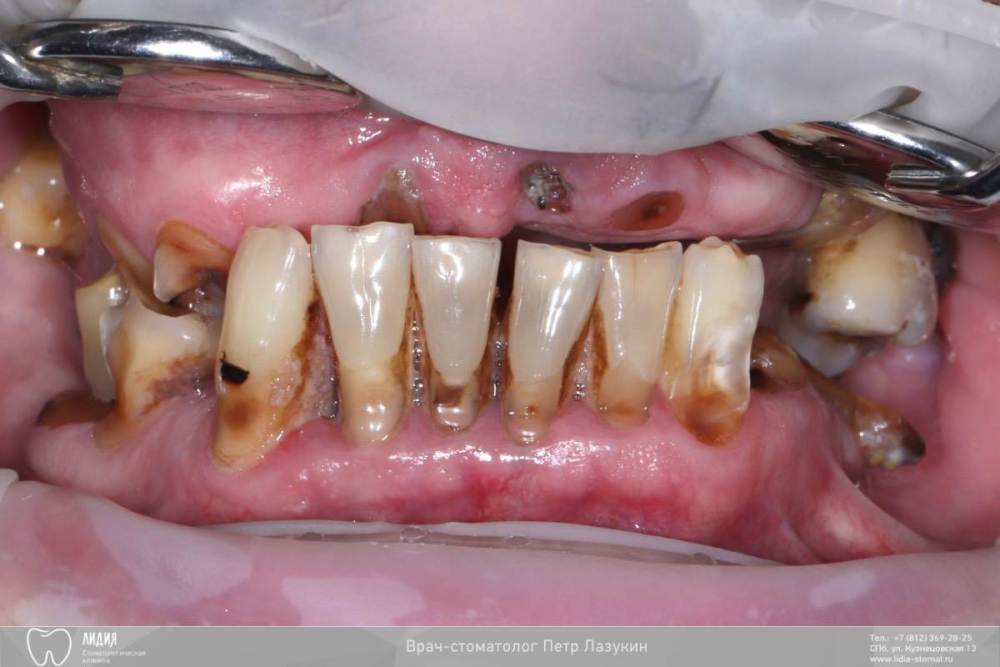

pit Опубликовано 9 августа, 2023 Поделиться Опубликовано 9 августа, 2023 Всем привет! Клинический случай тотального протезирования с опорой на имплантаты. Немедленная имплантация верхней и нижней челюсти с интервалом в 2 месяца. На верхней челюсти редукция, имплант 25 зуба транссинус. Отсроченная нагрузка, так как треснул гребень. Видео операции здесь https://youtu.be/YZM-A8we1WQ Постоянное протезирование ДЦ коронками с тирановыми каркасами. Верх с уровня МЮ, низ с уровня платформ. 2.mov 7 1 3 Ссылка на комментарий